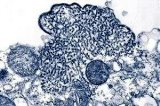

Ana Gabriela Mena, Directora General de Salud Pública, asegura que los casos reales de bronquiolitis en Jalisco podrían ser mas. Crédito: Archivo.

Aunque los pediatras reportan un incremento de bronquiolitis, causada por el Virus Sincitial Respiratorio (VSR), la Secretaría de Salud Jalisco (SSJ) tiene tan sólo 29 casos confirmados, señaló la directora general de Salud Pública, Ana Gabriela Mena Rodríguez.